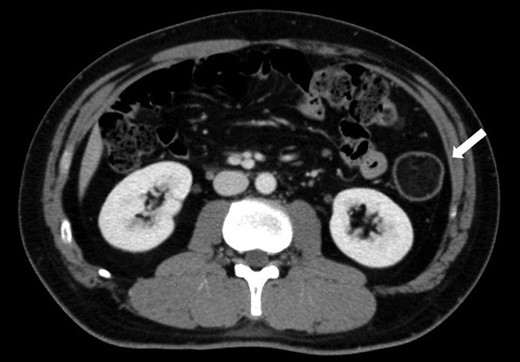

CT findings at the time of diagnosis: contrast-enhanced CT of the abdomen at the time of diagnosis revealed a solid mass measuring 5 cm in diameter with fat density in the descending colon (white arrow).